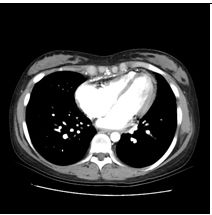

5. 29歲女性,主訴近年來有進展性雙腳水腫,全身倦怠,同時伴有運動性呼吸困難及腹部腫脹。病人在十多年前有紅斑性狼瘡,也因此四處求醫,誤信草藥,終致腎病末期之尿毒,施行血液透析治療。於今年4月24日赴中國接受腎臟移植,不意術後有諸多併發症,如尿路感染等,回國一直在門診治療。近多月來,上述症狀逐漸加劇,乃住院診療。理學檢查:血壓96/55 mmHg;心跳75/min規則;呼吸 18/min,尚屬平穩,病人呈現慢病狀,臉色蒼白,頸靜脈怒張,有Kussmaul's sign,胸部未有濕濁聲,心臟之point of maximal impulse (PMI)不清,S1及S2尚屬正常,未有心雜音,腹部未有肝脾可觸知,雙下肢有水腫。實驗室有WBC,5520;RBC,3,010,000;Hb,10.1 g/dl,BUN,40 mg/dl;Creatinine,1.79mg/dl,餘皆正常。其他胸部X光、心電圖及心臟電腦斷層 如圖示。請問本病人最可能的診斷是: (A) 左心臟衰竭 (B) 右心臟衰竭 (C) 冠心症 (D) 心肌病變 (E) 窄縮性心包膜炎 (constrictive pericarditis)